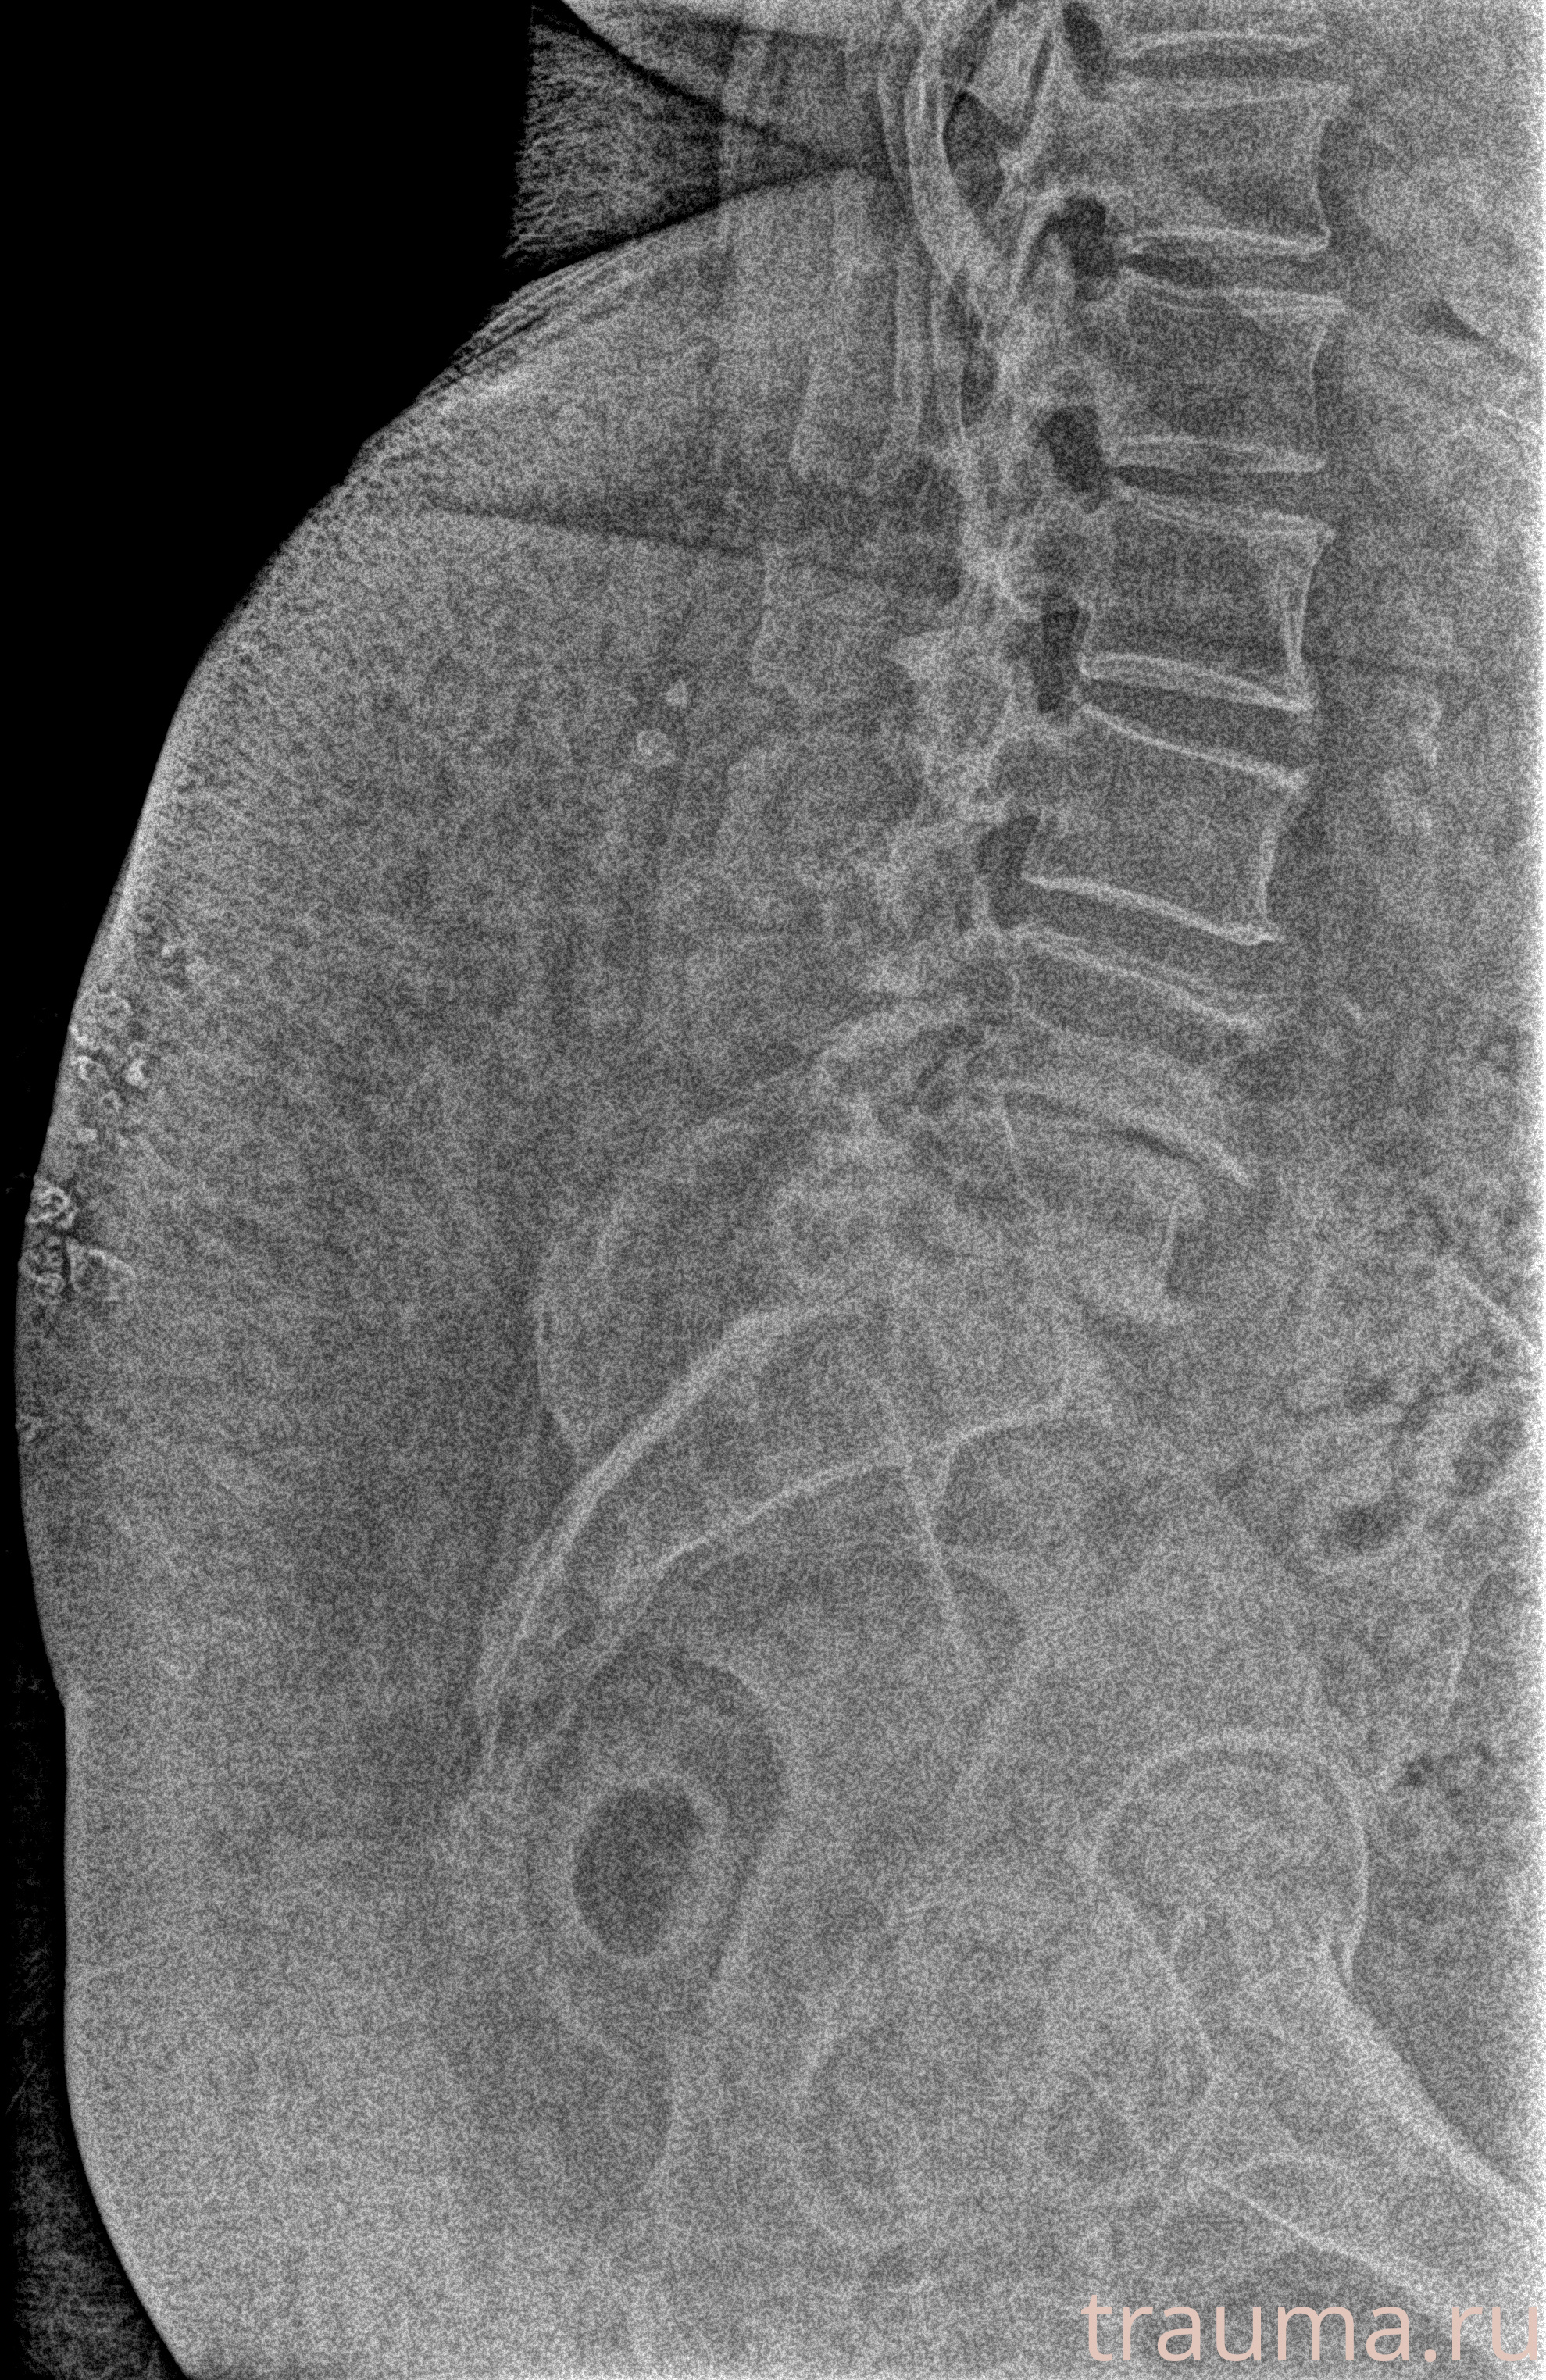

Рентген на дому: по вашему адресу приезжает врач-рентгенолог, травматолог-ортопед с мобильным рентгеновским аппаратом, проводит диагностику травмы или заболевания, делает необходимые рентгенограммы, дает рекомендации по дальнейшему лечению. Получить качественные снимки в домашних условиях возможно благодаря уникальной методике, разработанной МосРентген Центром для института  Склифосовского